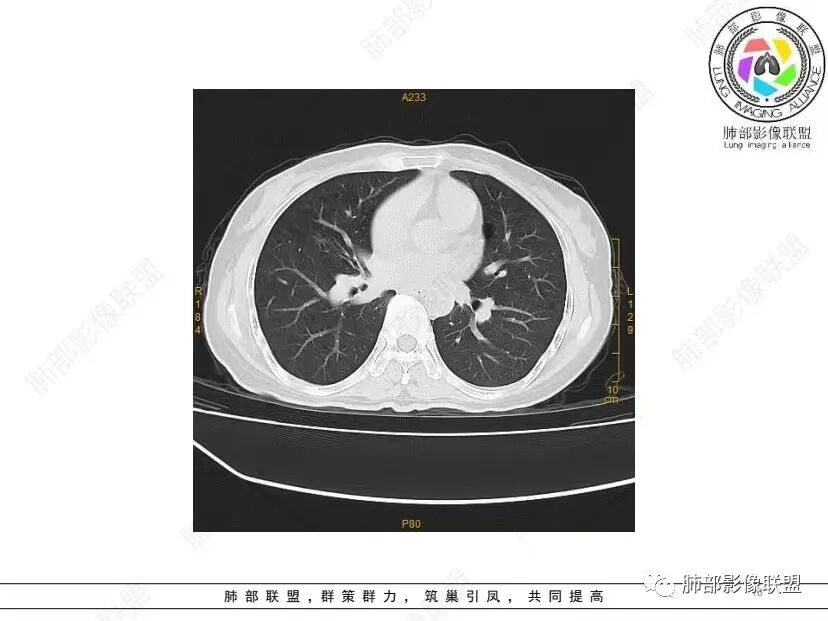

秦化君: 晨读 双肺不均匀散在多发囊状影,大小不等,部分囊形态欠规整,壁薄均匀,部分囊胸膜下平行。双肺少许斑片状磨玻璃影,边缘模糊。考虑BHD综合征。鉴别PCP,LIP。

红日初升: 中年女性,双肺多发气囊,背景干净,大小不一,下肺韧带旁较大,考虑BHD,鉴别LIP、LAM

宇宙: 中年女性,两肺多发大小不等薄壁囊状影,两肺纵膈胸膜下分布明显,考虑BHD,鉴别LAM

这个病例目前影像特点,多囊,囊主要位于下肺,胸膜下及小叶核心为主

伴随少许索条,而且这些病灶与囊不一定有相关性

囊的分布,PLCH基本可以排除

囊壁薄且均匀,光滑,形态规则,基本除外恶性

单纯囊,无斑片及其他实性病灶,感染不支持,可能的是:LAM、BHD、LIP

从囊的分布、大小,BHD可能性可能大一些,但是LIP、LAM都可以这样表现,具体诊断应该是这三种之一,影像缩小到这里我觉得就差不多了,结合临床考虑就行,不支持靠影像强下结论。

临床诊断BHD综合征需要满足一个主要或两个次要标准。主要标准包括:1、皮肤上至少发现5个纤维滤泡瘤,至少1个组织学证实;2、致病的FLCN种系突变阳性。次要标准:1、多发肺囊肿,双侧基底部,有或无自发性气胸;2、肾癌,起病早(<50岁)或多灶性或双侧;3、 BHD综合征一级亲属。BHD主要影像表现特征:1、两肺内肺囊肿:80%以上的BHD患者会出现肺内囊肿,且倾向于基底部近胸膜下分布,特别是纵隔侧肺膜下,囊肿形状不规则、囊肿可大可小,肺内囊肿多毗邻肺下动脉或静脉近端,胸部CT上囊肿分布和特点对诊断有提示意义。2、继发自发性气胸:BHD患者发生气胸风险是正常人的5倍,BHD患者的气胸发生率约为1/4,气胸复发率则高达59%。3、肾肿瘤:(常为双侧性、倾向于嫌色细胞组织学亚型)4、皮肤表现:(为面、颈部纤维性毛囊瘤、毛盘瘤)